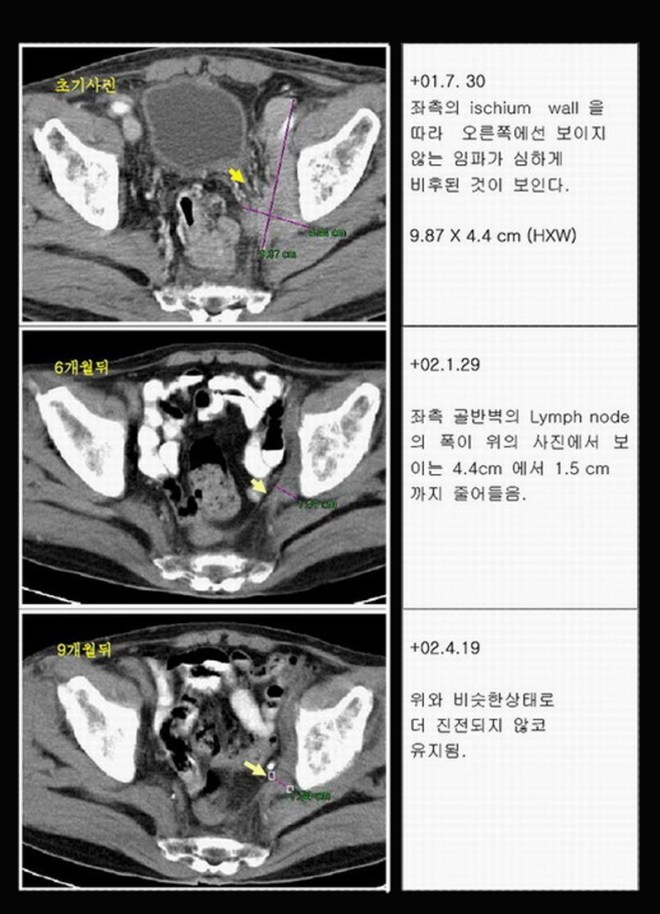

이 환자는 소음인 전립선암 환자로 당시 일산 백병원에서 전립선암 발견 이후 수술하려고 열었다가 고환절제술만 하고 수술을 못 하고 닫아버린 사례이다. 당시 병원에서 약 2개월 정도 생명연장이 가능하다고 사형선고를 받은 경우이다.

전립선암이 열어 보니 방광 대장을 다 침범하여서 거의 9cm 이상의 종양이 퍼져 있었고, 주변 ischial lymph node(골반 주위의 림프절)의 다발성전이가 있었던 분이다. 이후 본원에 와서 양방에서는 사용치 않는 양성 전립선비대를 억제하는 프로스카와 본원의 한방요법을 결합하여 전립선암이 거의 없어진 상태로  3년 이상을 정상생활을 하였고 그 후 술 담배를 다시 하기 시작하고 일년만에 다발성 폐전이가 되어서 폐렴합병증으로 사망한 사례이다. 자료를  2000 년도의 자료라 찾기가 어려워서 나중에 더 보충 자료를 넣어 보려고 하지만 본고에서는  2007 년도 본인이 삼성의료원의 산부인과 배덕수 과장 소개로 한의학의 암치료에 대한 강의를 초청받아서 갔을 때 자료를 가지고 이 환자의 사례를 설명해 보겠다.

위의 CT에서 보듯이 왼쪽 사진에 흰 화살표와 검은 화살표로 경계 지어지는 부분은 왼쪽 골반뼈에 접한 림프절인데 거의 10cm 이상을 육박하고 우측 사진에서는 위쪽은 방광벽, 아래로는 대장을 침범한 사진을 볼 수 있다. 워낙이 복부에 퍼져 있어서 바로 보고 닫았다고 한다.

1-6.jpg

이 환자는 두 달여의 치료에 좌측 사진에서 보듯이 왼쪽 골반벽의 종양이 모두 소실이 되어서 아래 사진에서 보이지 않고, 우측도 마찬가지로 이전 검은 화살표에서 보는 방광벽의 침범이 아래 사진에서는 정상 소변이 차서(조영제가 하얗게 보임) 면이 매끄럽게 다 없어지고, 아래 대장쪽도 다 소실이 된 상태이다.

이 환자는  이후  9 개월간의 사진을  이전 발표본을 그대로  수록해본다.